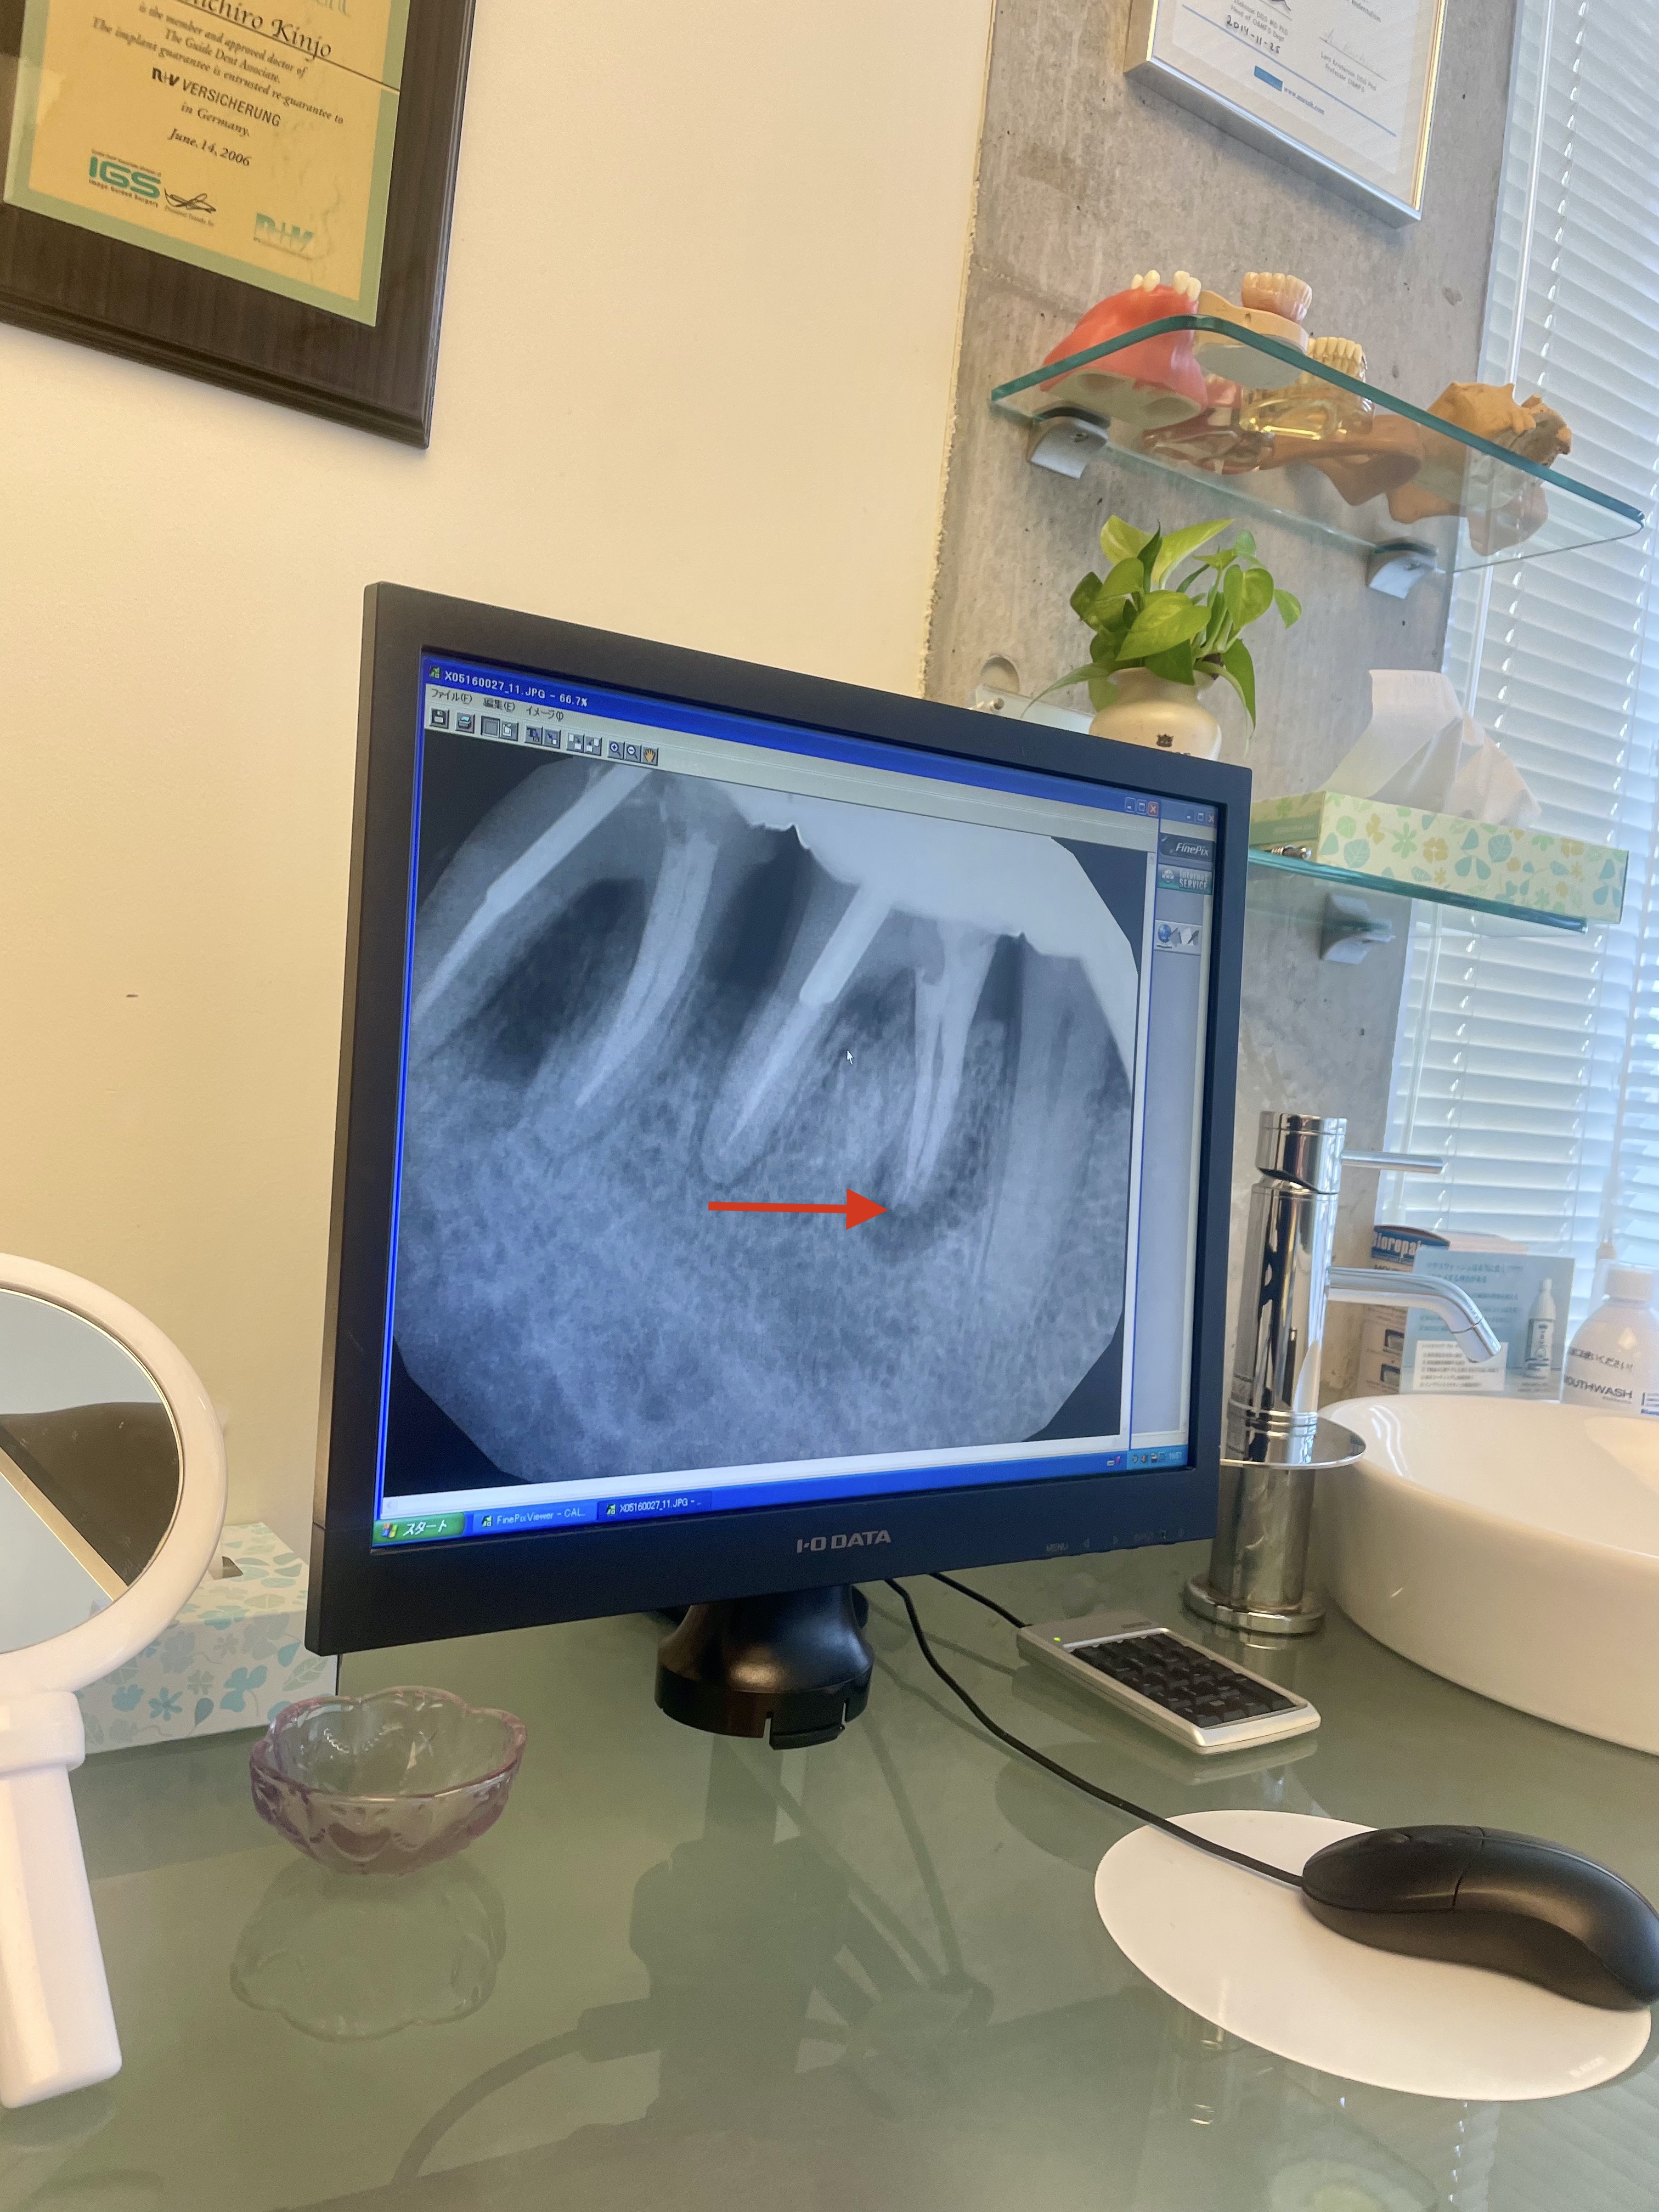

On the less positive side, my face swells up horribly again. I look like a monster and little children burst into tears when they see me. I go to see Kinjo sensei.

He discovers rot in the jawbone. This means losing another tooth. Boo!